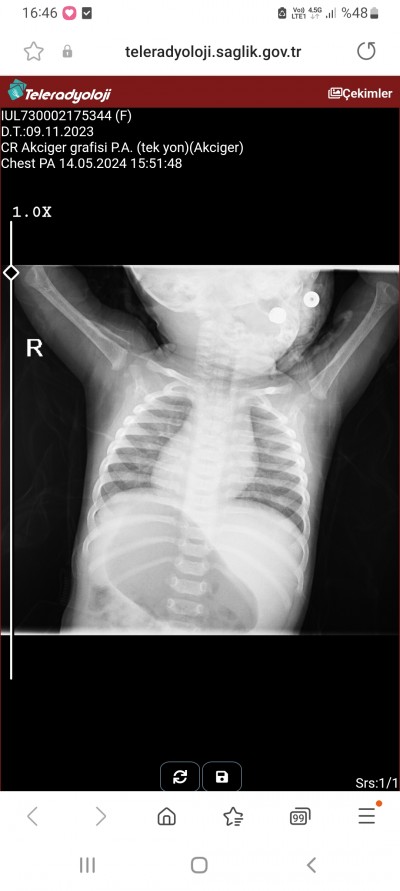

Doktorumuz bronsitten şüpheleniyor ama sonucu daha gostermedik anlayan var mı

image